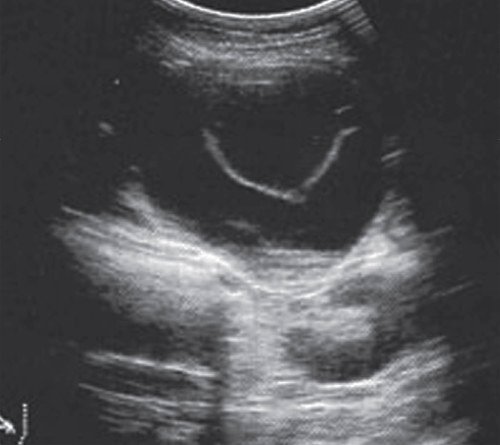

При УЗИ: в брюшной полости большое количество свободной жидкости. Селезенка не увеличена. ПЖ увеличена до 35x25x23 мм, диффузно неоднородная, смешанной эхогенности, проток железы не визуализируется. В сальниковой сумке в проекции головка - тело - хвост визуализируется жидкостное образование неправильной формы размером 141x36x113 мм, объемом около 280 мл, распространяющееся на забрюшинную клетчатку до уровня верхнего полюса левой почки. Печень не увеличена, однородной эхоструктуры, средней эхогенности. Внутрипеченочные протоки не расширены. Воротная вена - 11 мм, общий желчный проток - 8 мм. Желчный пузырь 86x30 мм, стенка 2 мм, в просвете большое количество мелких конкрементов. Заключение: "Конкременты желчного пузыря. Псевдокиста в проекции сальниковой сумки" (рис. 14).

В сальниковой сумке жидкостное образование неправильной формы размером 141x36x113 мм, распространяющееся на область хвоста железы и на забрюшинную клетчатку до уровня верхнего полюса левой почки.